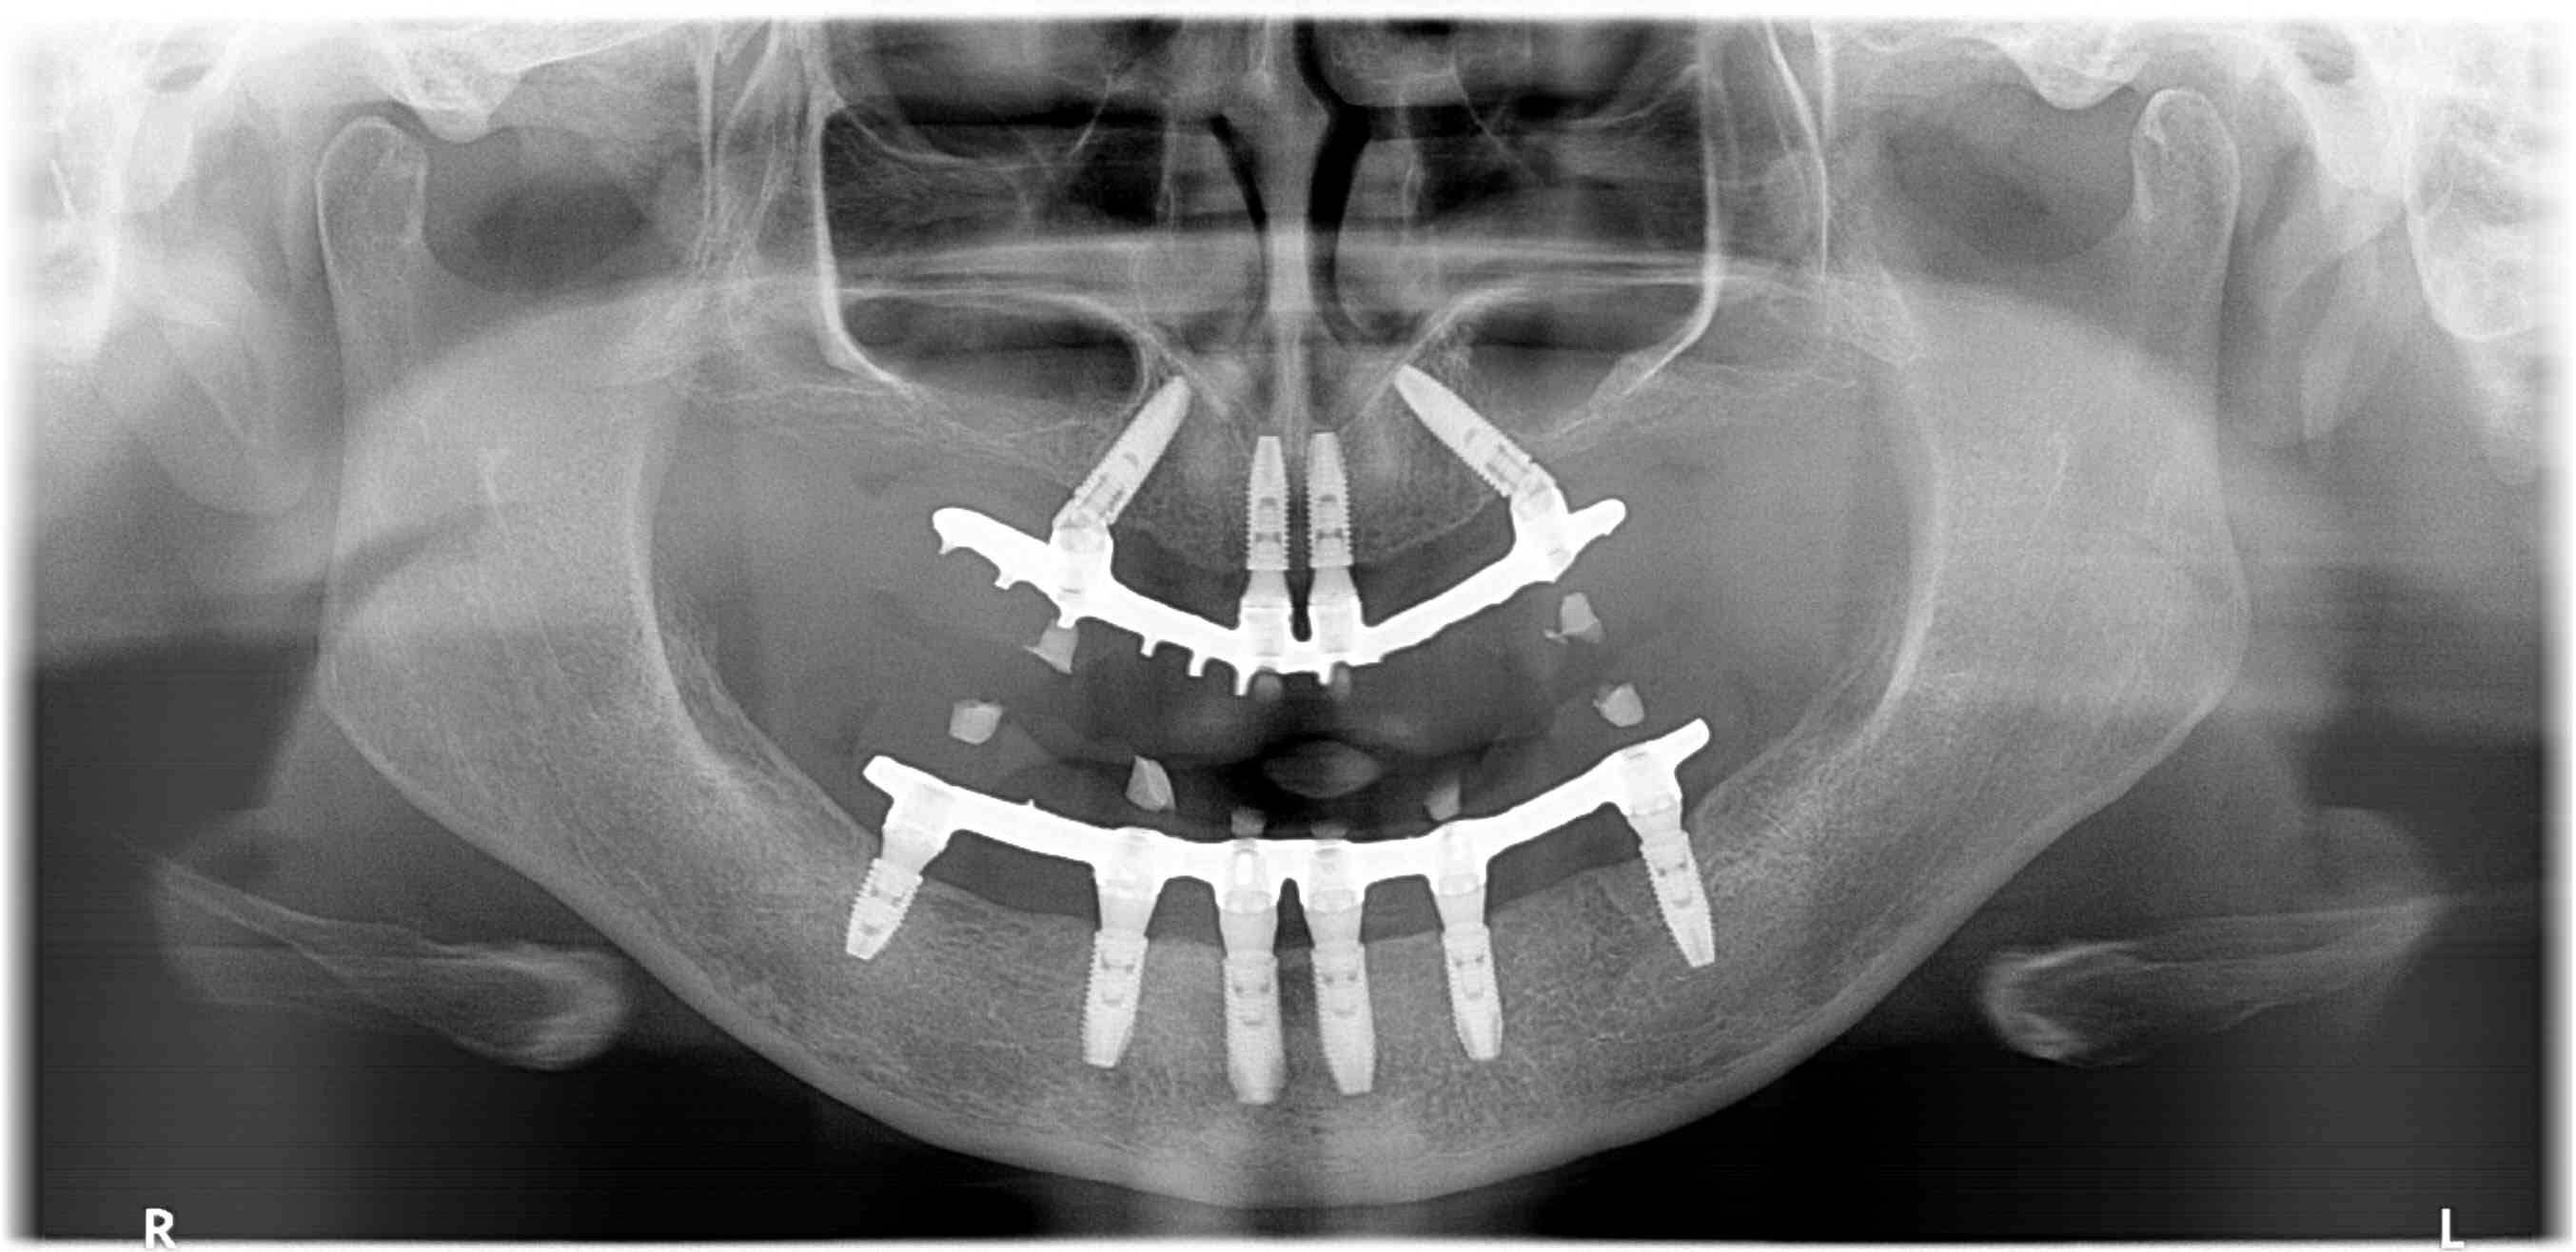

Implantációs fogpótlás – teljes rehabilitáció

AllOn4 és AllOn6 implantációs megoldással, halasztott implantációval és azonnali megterheléssel készítettünk rögzített ideiglenes pótlásokat.

rtga4_mutet_utan2